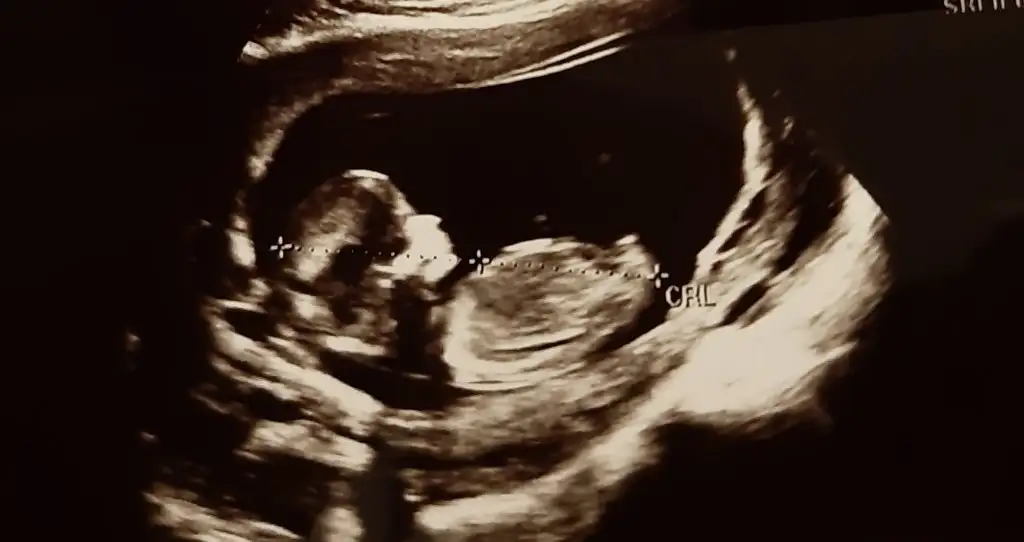

Kız gibi gibi diyorum net degil başka usg varsa tekrar tahmin ederimMerhaba bunlar da benim ultrason görüntülerim, yorumlar mısınız rica etsem. 11+3'deyiz![]()

Çok teşekkür ederim tüm ultrason görüntülerini paylaştım 10 gün sonra tekrar gideceğim inşallah doktorum da kız derKız gibi gibi diyorum net degil başka usg varsa tekrar tahmin ederim